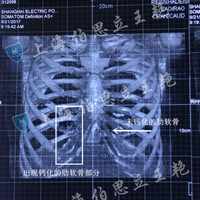

关于肋软骨钙化是否还可以进行鼻部多项手术?今天来简单解答一下: 1,如何判断来软骨是否钙化? 一般来说年龄越大肋软骨钙化的几率也就越高,但这种情况也并非一定的,在我工作中,遇到钙化最小年龄的只有18岁,那么如何准确判断来软骨钙化呢,术前辅助专业检查是非常有必要的,因为我们仅凭认为目测判断无法准确评估是否钙化。 2,肋软骨钙化是否还可以做鼻部多项手术? 肋软骨钙化也需要判断严重程度,如果钙化